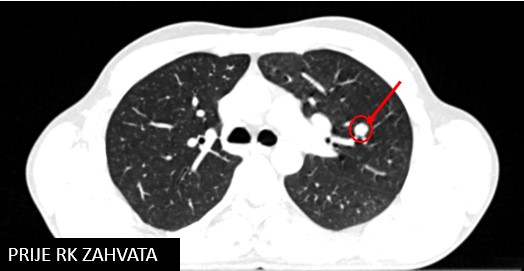

SBRT meta pulmonis (11/2018; 7/2019)

Rezultat – 51 mjesec nakon RK

Potpuni nestanak tretirane lezije